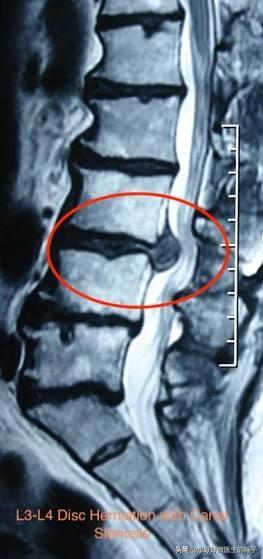

而根据腰椎不同部位的问题,会诱发不同部位的症状,大家看下图就会基本明白不同位置的神经根出现了炎症以后疼痛的大致范围。

而将纤维传递到膝盖的神经位于腰部第二、第三和第四腰椎水平处。如果像椎间盘突出或关节炎导致的骨质增生压在这些部位的神经上,那么膝盖部位可能会感到疼痛,当突出位于腰二椎体的时候,患者就会表现为臀部的疼痛,然而一般这种情况是比较少见的,因为一般的腰椎间盘突出多数都位于腰4-5和腰5-骶1这两个节段。